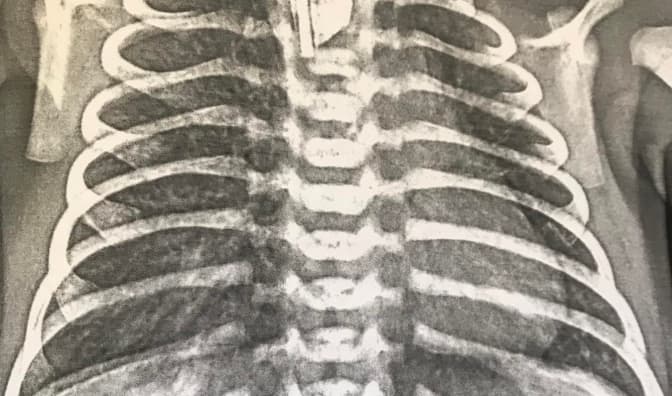

CityLifeЛьвівські хірурги уперше провели корекцію грудної клітки методом «магічної струни»

Львівські хірурги уперше провели корекцію грудної клітки методом «магічної струни»

02 лютого 2023, 12:29